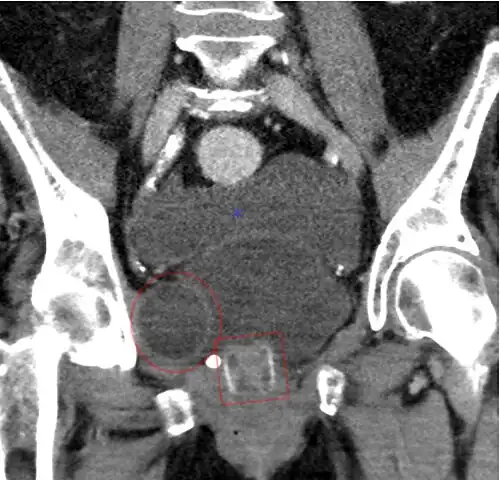

Tomografia computadorizada (reconstrução coronal) mostrando um AMS 800 em uma mulher.